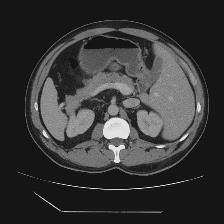

Medical image segmentation is one of the most fundamental tasks concerning medical information analysis. Various solutions have been proposed so far, including many deep learning-based techniques, such as U-Net, FC-DenseNet, etc. However, high-precision medical image segmentation remains a highly challenging task due to the existence of inherent magnification and distortion in medical images as well as the presence of lesions with similar density to normal tissues. In this paper, we propose TFCNs (Transformers for Fully Convolutional denseNets) to tackle the problem by introducing ResLinear-Transformer (RL-Transformer) and Convolutional Linear Attention Block (CLAB) to FC-DenseNet. TFCNs is not only able to utilize more latent information from the CT images for feature extraction, but also can capture and disseminate semantic features and filter non-semantic features more effectively through the CLAB module. Our experimental results show that TFCNs can achieve state-of-the-art performance with dice scores of 83.72\% on the Synapse dataset. In addition, we evaluate the robustness of TFCNs for lesion area effects on the COVID-19 public datasets. The Python code will be made publicly available on https://github.com/HUANGLIZI/TFCNs.

翻译:医学图像分解是医学信息分析的最根本任务之一,到目前为止已经提出了各种解决办法,包括许多深层次的学习技术,如U-Net、FC-DenseNet等。 然而,高精度医学图像分解由于医疗图像中存在固有的放大和扭曲,以及存在与正常组织密度相似的损伤,因此仍是一项极具挑战性的任务。在本文件中,我们建议TFCN(全面革命稠密网络的传输者)通过向FC-DenseNet引进ResLear-Transerferent(R-Transerfor)和Culvacial线性关注区(CLAB)来解决这一问题。TFCN不仅能够利用CT图像中更多的潜在信息来提取特征,而且还能够通过CLAB模块更有效地捕捉和传播语性特征和过滤非神经性特征。我们的实验结果表明,TFCN可以在Syapseion/SymblyDDS上以83CN-72 ⁇ 的分数实现状态。此外,我们在Synapse-DRIS数据设置上,我们还将评估CUTFTFI/LIS的可靠度。